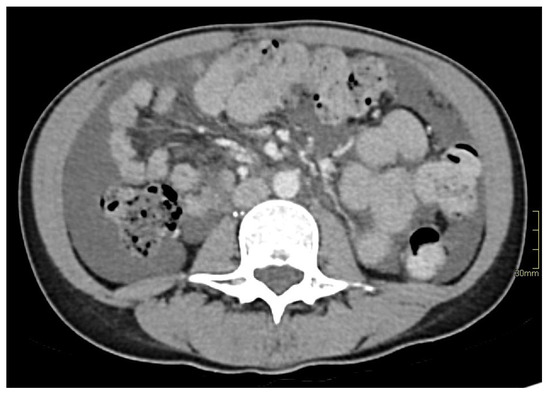

2. Case Report

3.2.3. Imaging